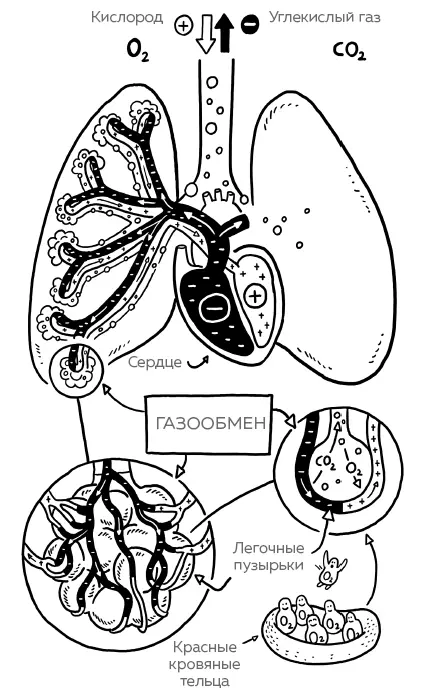

Пассажиры маленьких красных «шлюпок» – молекулы кислорода. Они запрыгивают в клетку-лодочку, когда капля крови проносится по тонкому сосуду в легком – он еще называется капилляром. Каждый раз при вдохе кислород вместе с другими газами устремляется по разветвляющимся – и чем дальше, тем тоньше и извилистее – дыхательным путям в крошечные пузырьки – альвеолы. Из-за этих пузырьков легкие внутри похожи на губку.

Предположительно, в легком человека находится как минимум 300 миллионов альвеол.(Но точно еще никто не подсчитывал.) Когда после вдоха альвеола раздувается, она может достичь четверть миллиметра в диаметре. При выдохе она съеживается на пятую часть. Губчатая структура с бесчисленным множеством маленьких пузырьков нужна для того, чтобы мы при каждом вдохе вбирали как можно больше кислорода. Для этого поверхность, на которой вдыхаемый воздух встречается с кровью, должна быть по возможности максимально большой. По приблизительным оценкам, поверхность всех альвеол в одном легком составляет примерно 100 квадратных метров – не всякая трехкомнатная квартира может похвастаться такой площадью!

От воздуха в альвеолах протекающую по капиллярам кровь отделяет очень тонкая стенка. Для пассажиров эта стенка не препятствие: молекулы кислорода запросто через нее проходят, как делал это Гарри Поттер с друзьями, когда им надо было попасть на поезд в Хогвартс, стоящий на платформе 9 3/ 4. Но почему кислороду надо лезть напролом? А все потому, что он следует единому закону природы, высшая цель которого – сбалансированность: во вдыхаемом воздухе кислорода много, а в протекающей мимо в момент вдоха крови он в дефиците. Вот поэтому молекулы кислорода – эти стремящиеся установить равновесие пассажиры – и прут напролом.

Рис. 2